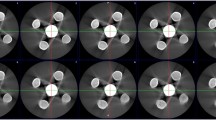

A single examiner assessed all CBCT scans in OnDemand3D software (CyberMed, Seoul, Republic of Korea; Fig. 2). On axial reconstructions, six circular regions of interest (ROIs; diameter, 5.4 mm) were selected around the middle height of the three cylinders comprising a total of 18 ROIs. To determine the ROIs, the examiner selected the perimeter of the circular-shaped sample (diameter of 5.4 mm) and drew a vertical line across its centre. This line served as a reference to symmetrically arrange the upper and lower ROIs. Then, the remaining four ROIs were placed such that they were tangent to the circular sample area and to each other, as shown in Fig. 3. The same ROIs were selected in an area under no effect of the cylinder-related image artefacts (control area), 5.4 mm below the lower edge of the cylinders. Standard deviation (SD) of grey values was obtained from the ROIs around the samples as a measure of artefact expression (grey value variability). Importantly, higher SD of grey values represents greater artefact expression and worse image quality. After 90 days, 50% of the images were reevaluated to assess the reproducibility of the method.